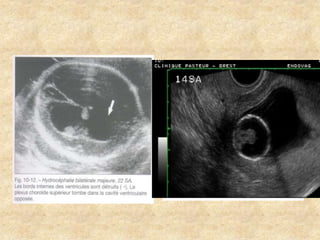

Contours de la boîte crânienne

-Aspect des ventricules latéraux

° Taille :Plexus

occupant toute la

largeur de la région de

l’atrium

°Mesure précise du

diamètre

atrial

°Forme des cornes

antérieures

et postérieures

°Aspect des parois

°Contenu